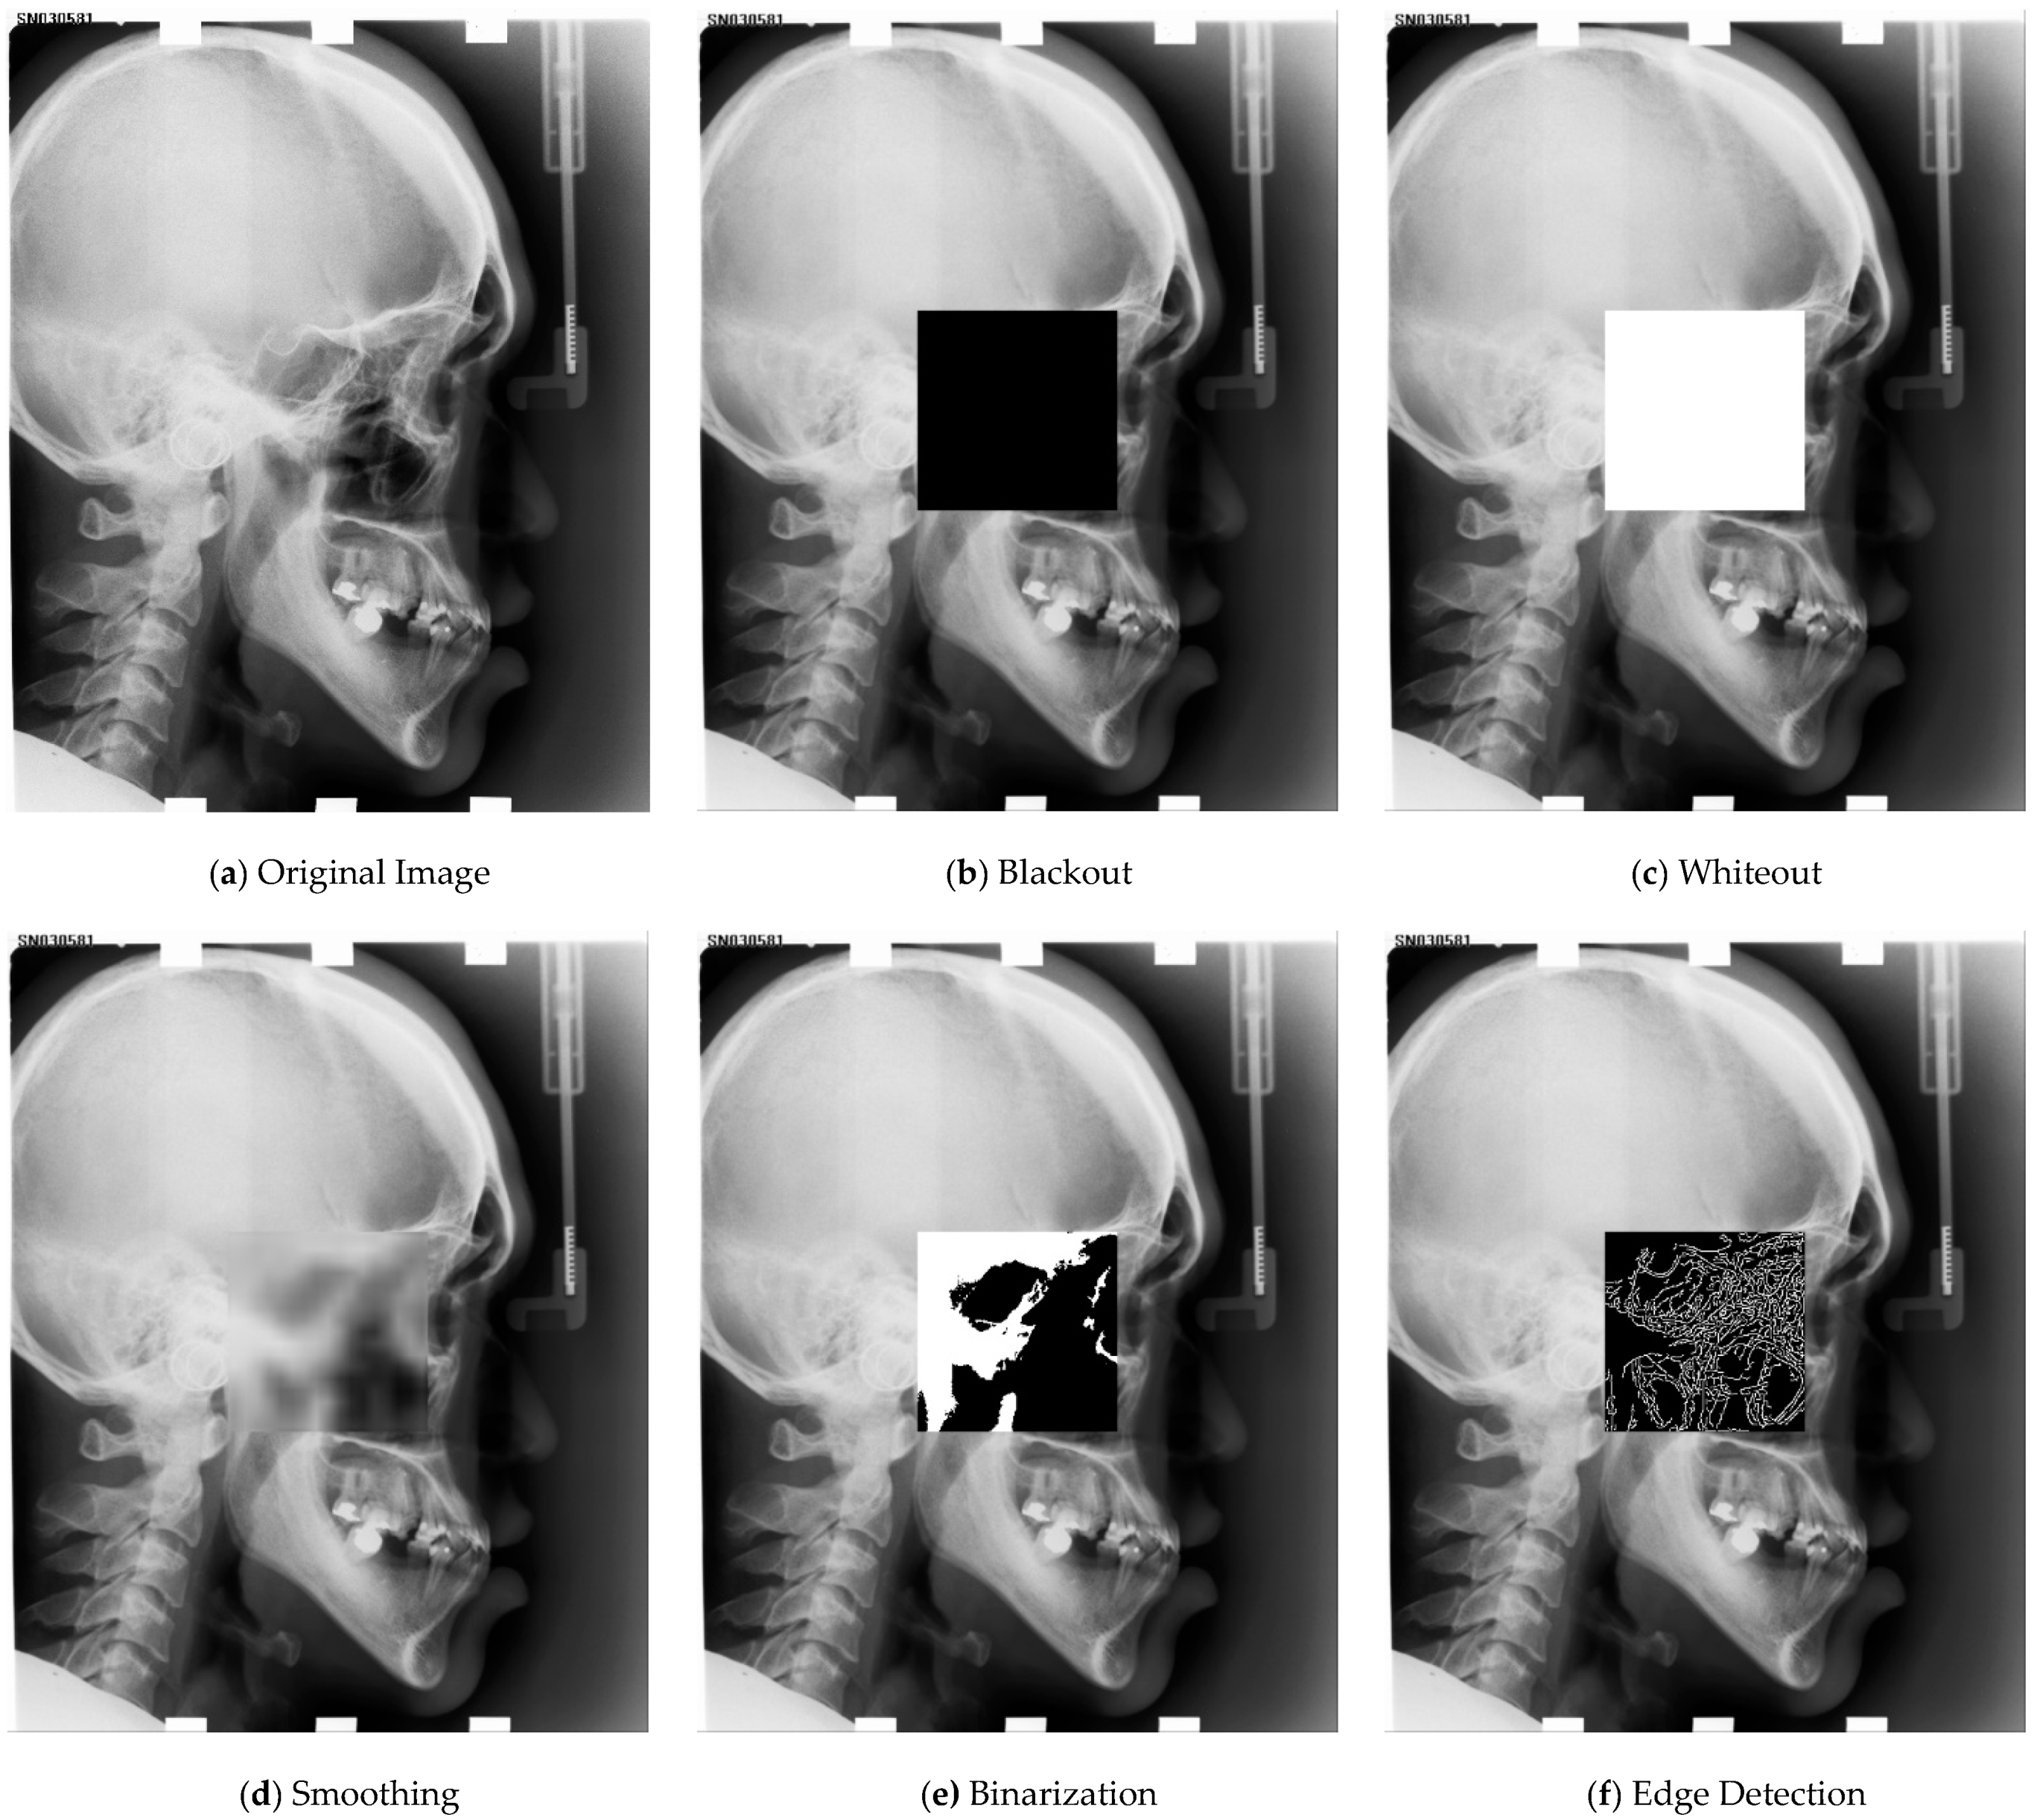

Line 4 deserves attention. The perturbation can be an operation that reduces the information of the input image. In our implementation, we used an operation of smoothing, blackout, whiteout, binarization, or edge detection for the perturbation. The perturbation operation is applied to a patch whose location and size are decided randomly, as explained in Algorithm 2. Algorithm 2 is described in detail in Section 3.3. After altering the patch in line 5, the augmentation is applied to the perturbed image. Rotation, translation, rescale, and color-jitter are applied as augmentation operations. The augmented image is used as input to the network in line 6. Figure 2 illustrates the altered image with each of the 5 perturbation operations.

3.3.1. Blackout and Whiteout

The blackout changes all the pixels in patch p into black, being value 0. The whiteout changes all the pixels in p into white, being value 1. These operations are the extreme cases, in the sense that they remove all the information within the patch. The network should look at neighboring regions outside of patch p, so as to learn the landmarks within p. Figure 2b,c show examples of the blackout and whiteout, respectively.

3.3.2. Smoothing

This algorithm reduces the information in p to some extent, according to the randomly sampled α. Therefore, the network should learn the representation using both the local information in patch p, and the global information outside p. Figure 2d illustrates an example image perturbed by smoothing.

3.3.3. Binarization

Binarization converts pixels in p into black (0) or white (1). The threshold value is obtained from the Otsu algorithm [37], The threshold value in Otsu algorithm is determined such that the value maximizes inter-class variance by separating pixels into two classes, background and foreground. In our perturbation, a value generated from the normal distribution N(μ, σ2), where μ = 0.2, σ = 0.15 is added to the threshold. The resulting threshold is applied to the patch p to binarize. Figure 2e illustrates an example image perturbed by binarization. As was the case for smoothing, the network should learn the representation using both the reduced local information in patch p, and the global information outside p.

3.3.4. Edge Detection

Edge detection is performed using Canny edge detection algorithm [38], resulting in pixels with 0 (non-edge) or 1 (edge). The sigma value for the Canny edge detector is determined by random sampling from N(μ, σ2), where μ = 3.5, σ = 1.5. A larger value of sigma results in coarser scale edges and greater noise suppression effect.

Figure 2. Visualization of perturbed images, (a) is the original image, (bf) are the perturbed images, (b) is perturbed with blackout, (c) is perturbed with whiteout, (d) is perturbed with smoothing, (e) is perturbed with binarization, and (f) is perturbed with edge detection.